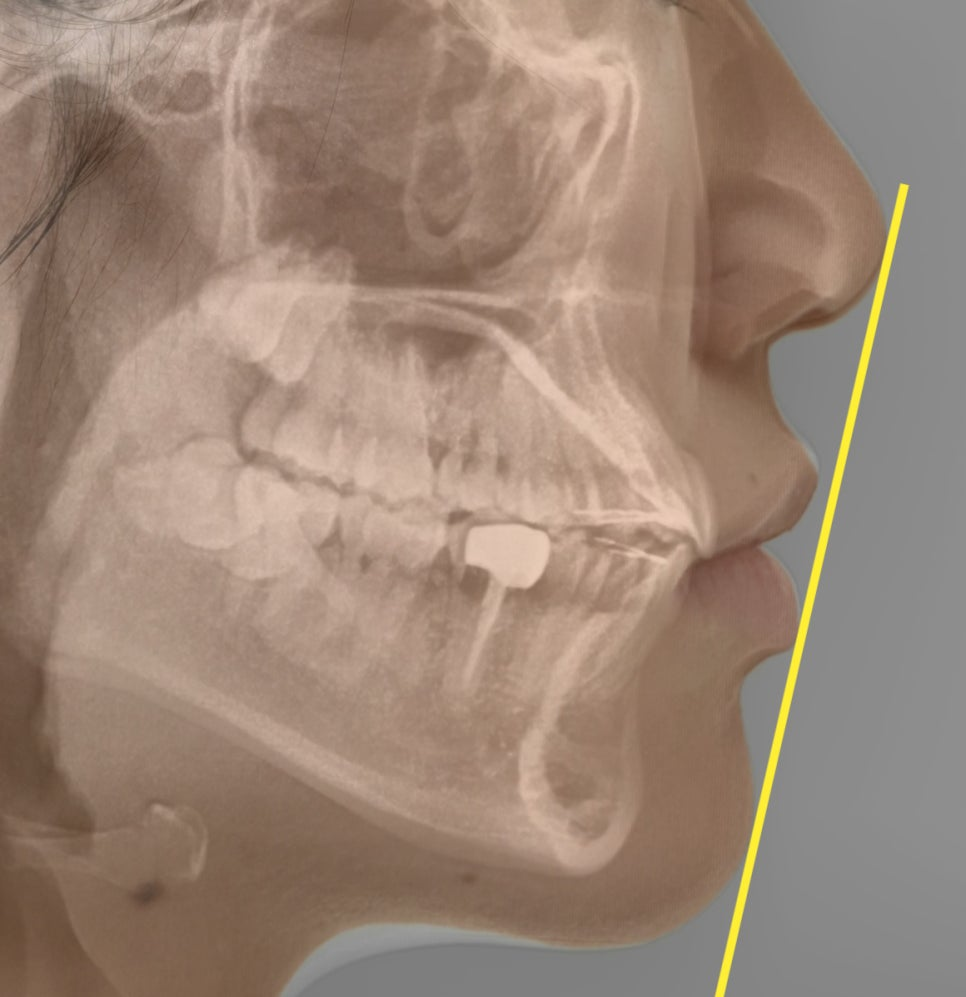

실제 안모를 확인해 보았을 때도

치열이 삐뚠 것이 눈에 띄었으며,

다행히 코끝과 턱 끝을 이은 심미선을

기준으로 하였을 때

입술이 살짝 닿았지만

문제가 되는 돌출감은 없어 보였습니다.

24.01.20

얼굴의 길이가 수직적으로

짧은 단안모에 속하였습니다.

세팔로 사진과 측면 사진을 보았을 때

전보다 안정적으로 입술과 심미선의 거리가

확보된 것을 확인할 수 있었습니다.